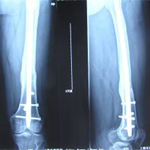

張某,男,50歲,因“左股骨骨不連”入院。植骨+PRP治療后8月完全愈合。

術前

術中

術后完全愈合